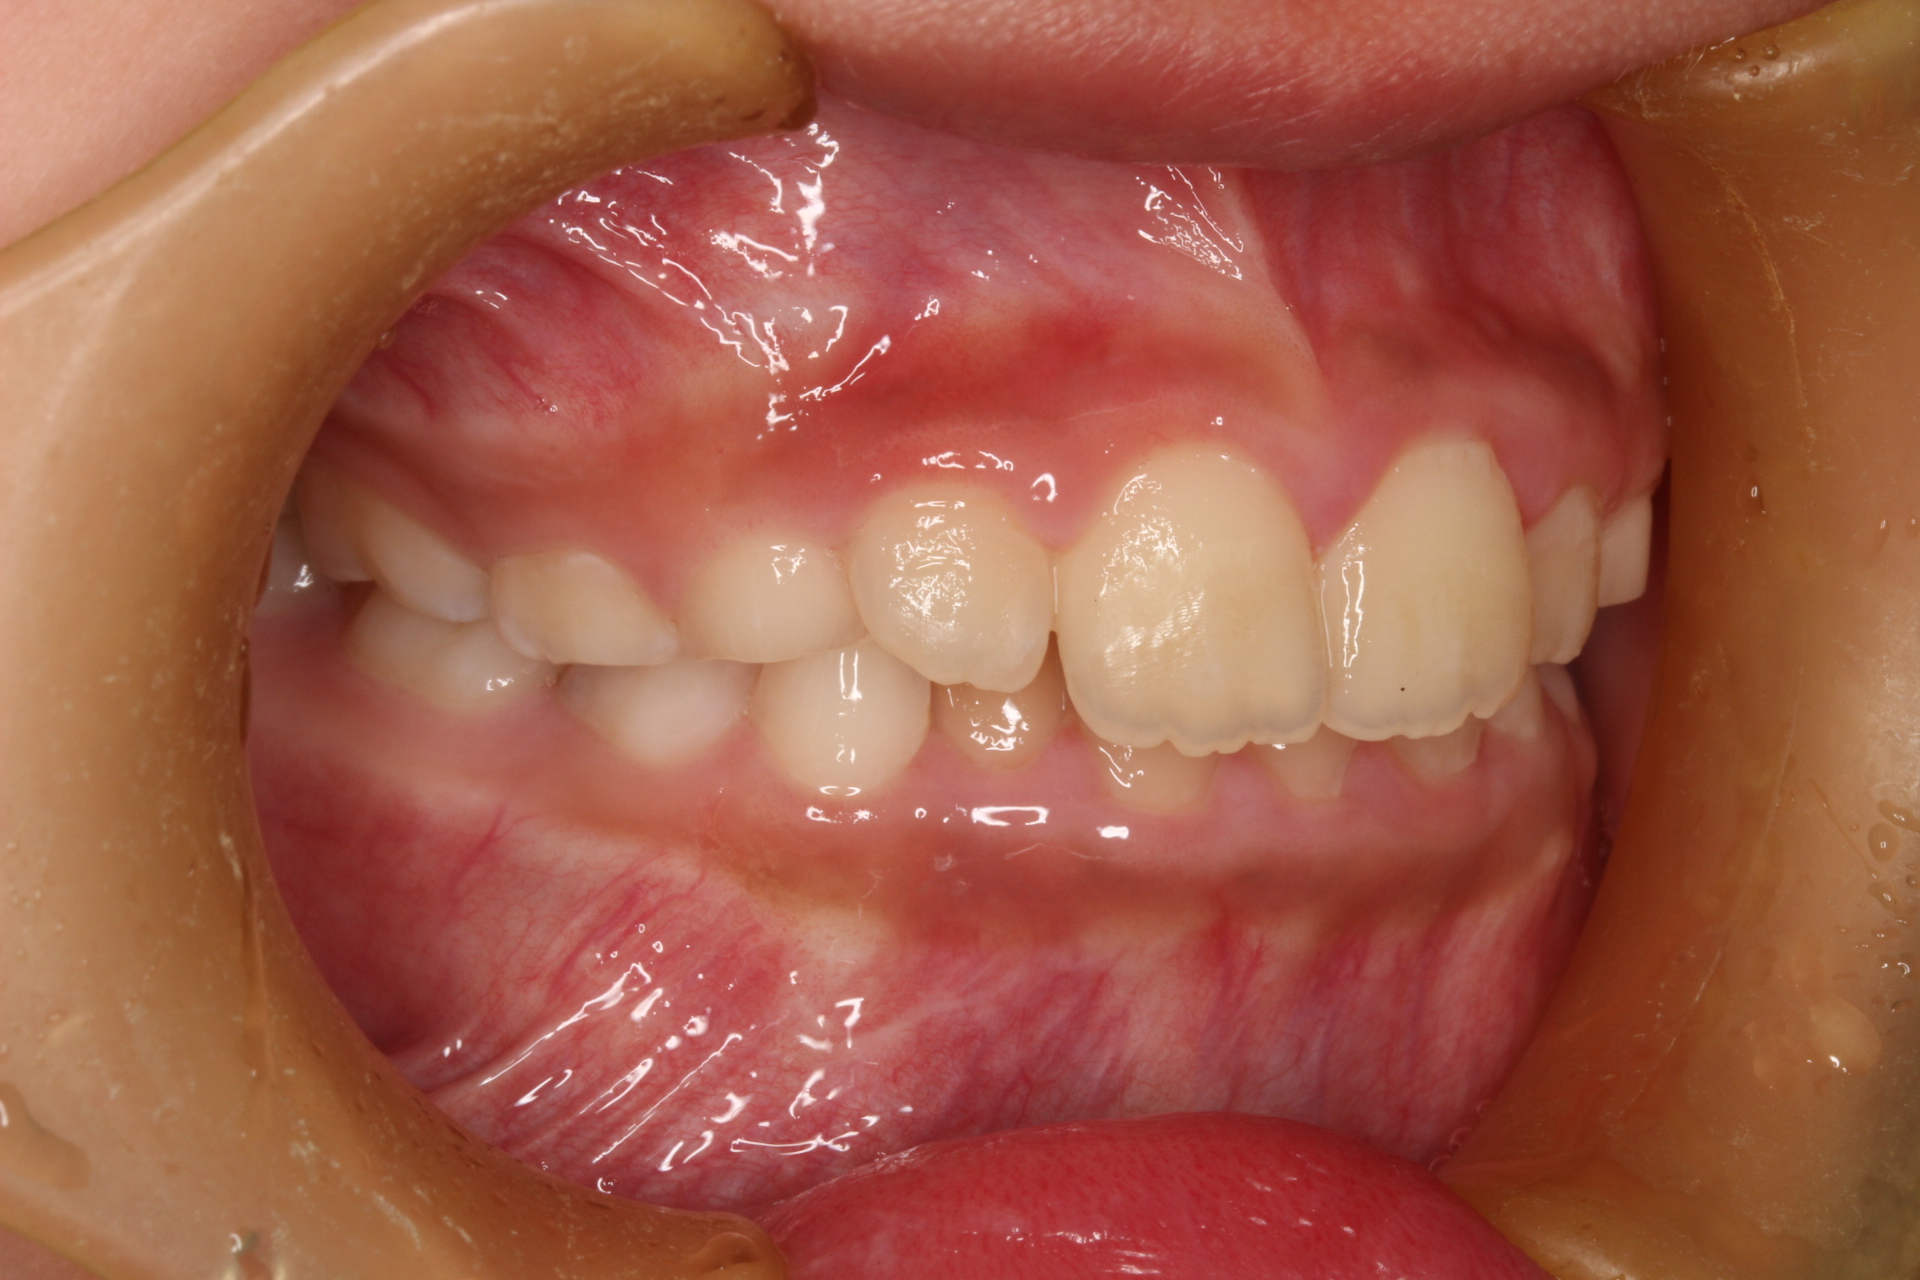

矯正術前:右側

矯正術後:右側